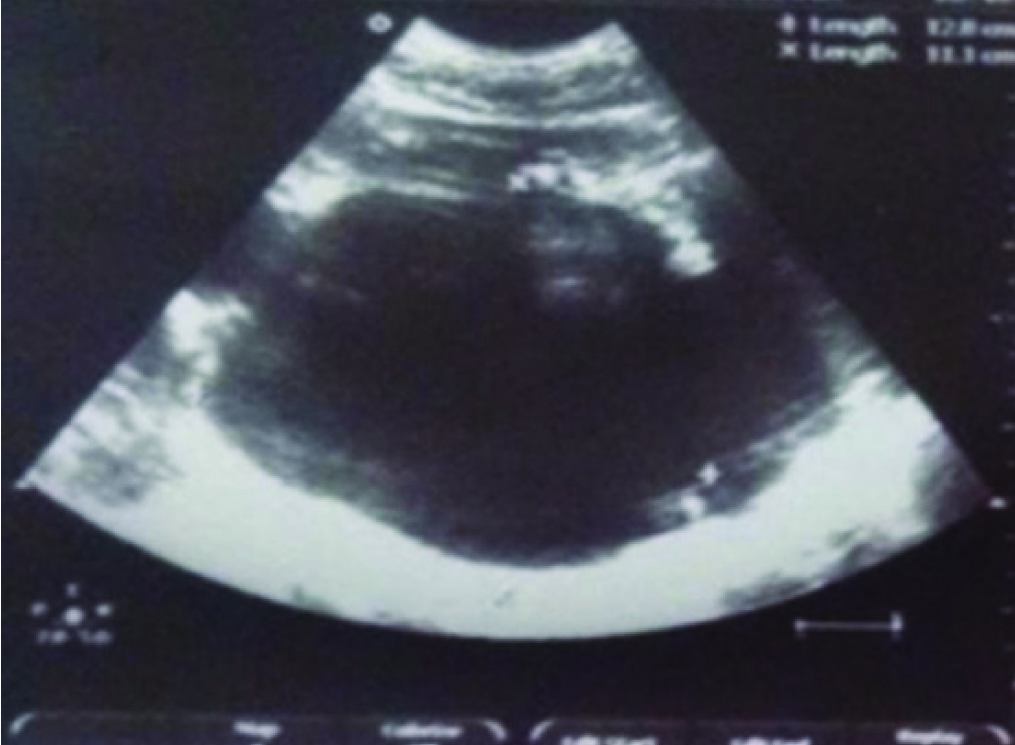

A 32-year-old male, presented with pain in abdomen, distension, breathlessness and anuria for three days. He was diagnosed elsewhere to have Acute Kidney Injury (AKI) and had undergone one session of Haemodialysis (HD) two days before presenting to our institute. He was pale with a pulse rate of 110/min, systolic blood pressure of 90 mm Hg and tachypnea (respiratory rate 30/minute). He had left sided abdominal fullness with a firm mass palpable in the left hypochondrium and lumbar regions. His blood urea 235 mg/ dl, serum creatinine was 8.2 mg/dl and haemoglobin was 6.5 g/dl. He was stabilised haemodynamically and HD was done. Ultrasound (US) showed an enlarged left kidney and a lower pole anechoic collection with septations, 11.4 x 9.9 x 8.6 cm [Table/Fig-1] and diagnostic aspirate was bloody. NCCT of kidneys showed left perinephric collection with compressed kidney [Table/Fig-2].

Ultrasound showing enlarged left kidney with 11.4 x 9.9 cm lower pole anechoic collection.